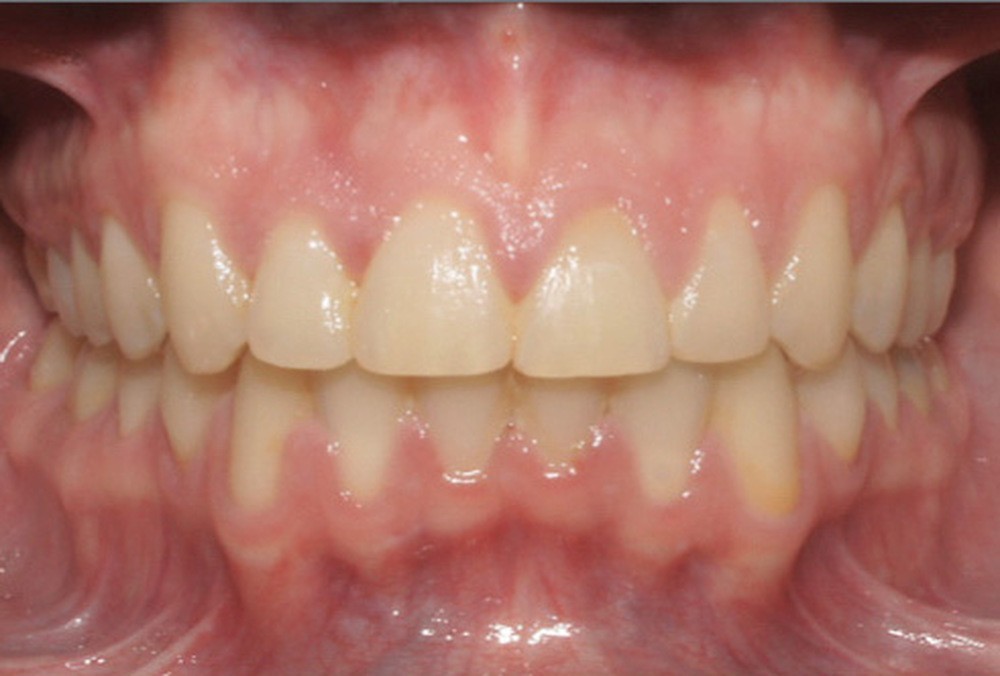

Discussion (fig. 4 à 7)

Le traitement a duré vingt-quatre mois. Le décalage de classe II complet à droite a nécessité une mécanique importante impliquant une bonne coopération du patient ainsi qu’un contrôle rigoureux des effets parasites. Les documents de fin de traitement nous montrent une normalisation des rapports incisifs. La correction de la classe II a entraîné une vestibulo-version de l’incisive mandibulaire qui reste néanmoins acceptable, et qui participe à la fermeture de l’angle interincisif, recherchée dans le traitement des classes II division 2. Les fonctions ont été rééduquées. Sur le plan esthétique, les améloplasties réalisées sur les bords libres de 12 à 22 ont permis d’effacer les séquelles de la supraclusion et participent à l’harmonisation du sourire.